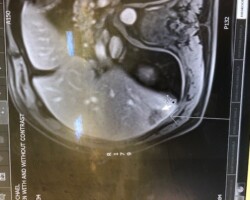

Resection of large retroperitoneal sarcoma including right and transverse colectomy and right hepatectomy